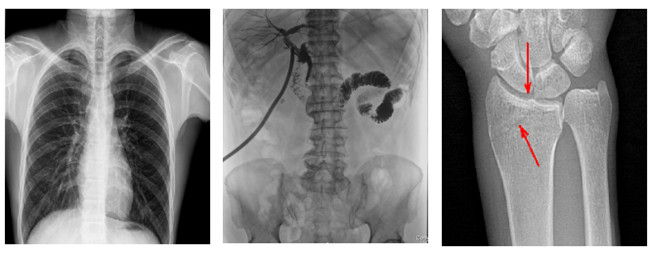

普利德多功能悬吊动态DR,搭载100μm高品质动态平板探测器,不仅满足常规的数字化X线全身摄影需求,同时还拥有数字摄影、数字透视、数字造影、全景拼接等多种功能,极大地拓展了X线检查在临床应用范围,为医院临床应用带来更多实用价值?;诎傥⑵桨宓母咔宄上瘢枷袂逦扔敕直媛矢?,可满足不同检查部位对细节成像的高品质要求,在胸腹部、脊柱等复杂骨骼和软组织的摄片上应用,更便于观察隐匿性病灶,精准识别疑难病症。

不同于静态DR拍摄隐匿性病灶时,由于组织重叠病灶难辨,耗费时间更长且易漏诊、误诊,普利德多功能悬吊动态DR可通过动态实时连续成像,对于重叠部位病灶或者易被遮挡的病灶进行多角度动态观察,毫秒级时间内实现动静态转换点片,快速、精准完成摄片。比如隐匿性肋骨骨折,可在透视下观察患者的呼、吸过程,避开重叠影像,快速点片,保证检查部位的病症不被遗漏,实现精准诊断。